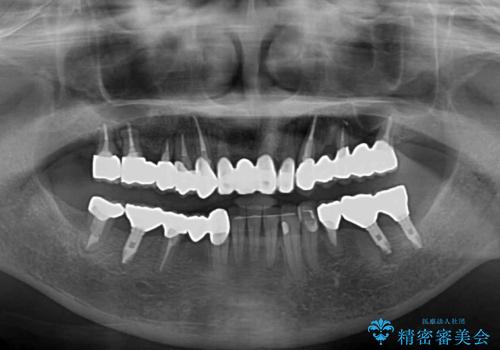

放置したインプラントとインビザライン 全顎リカバリー治療

- 以前通院していた医院で、奥歯のインプラント埋入、前歯部のインビザライン矯正を行ったものの、そのまま放置してしまったとのことで来院された患者様です。

下顎前歯や上顎奥歯などをワイヤー装置により部分矯正を行い、歯列を整えた上でインプラン部分を含めてオールセラミッククラウンにて補綴治療を行うこととしました。

インプラント上の仮歯がボロボロになり、前歯に非常に負担のかかる状態であったため、早急に奥歯の仮歯を修復し、矯正治療、奥歯の補綴治療、前歯の補綴治療と順々に進めて行きました。